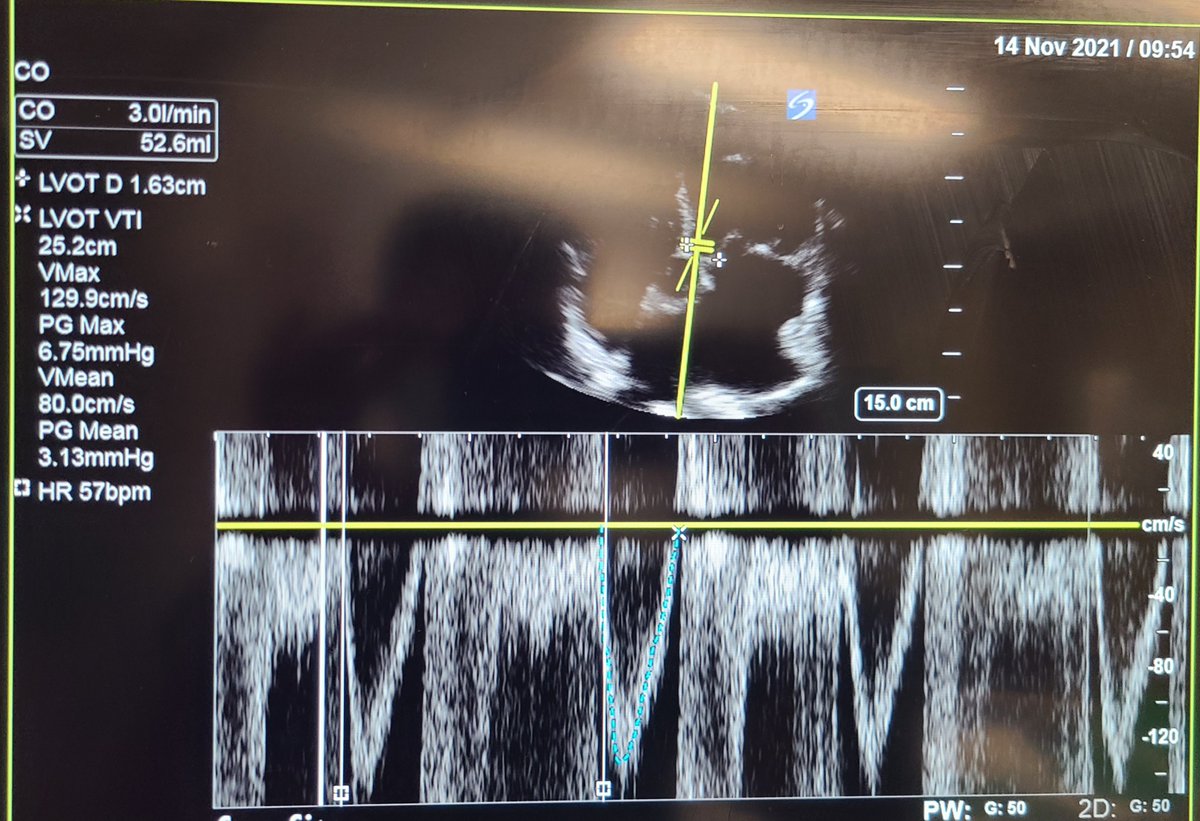

EPSS and LVOT VTI

Echocardiogram demonstrates preserved EF without evidence of RV pressure overload, no overt pericardial or pleural effusion but confirms low cardiac output driven by bradycardia (CO calculated 3L/min)

Images were obtained following administration of IV levothyroxine and further history taken revealed patient was recently placed on digoxin!